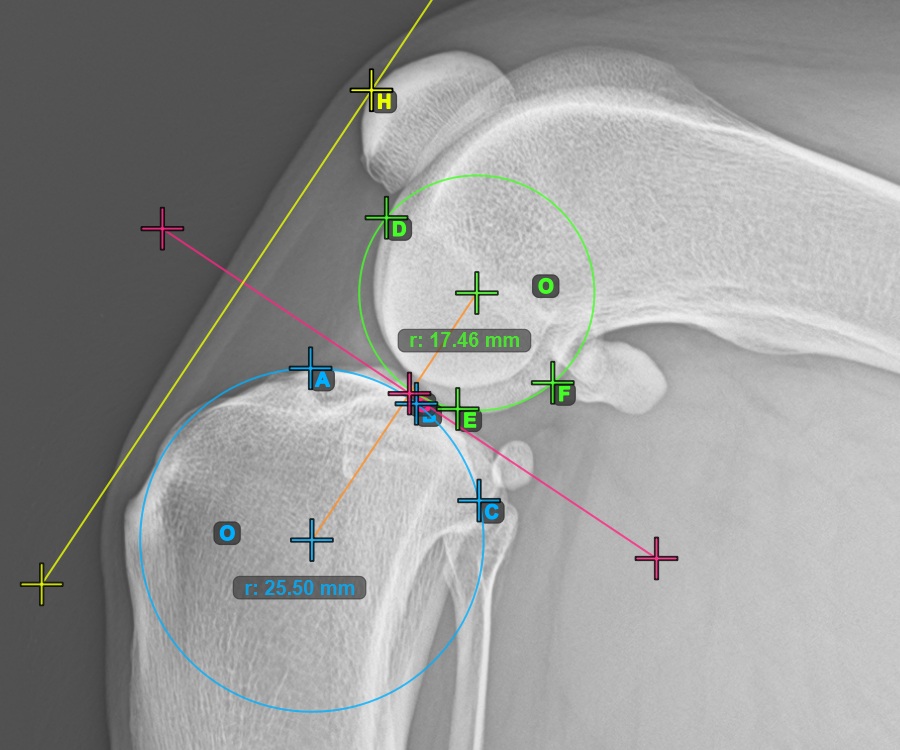

Folytassa a mérést a három pont megjelölésével a Condylus Femoris ízületi felszínén.

Jelölje meg a három pontot a combcsont fő condylusán (Condylus Femoris). A sorrendtől függetlenül ügyeljen arra, hogy megjelölje a legfelső pontot, a legalacsonyabb pontot és a Condylus Femoris középpontját. A három pont alapján a rendszer automatikusan létrehoz egy kört.

A lenti kép a Condylus Femoris-on elhelyezett három pont tipikus elhelyezkedését ábrázolja.